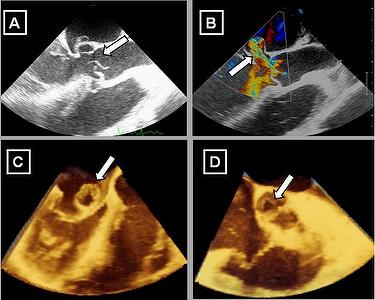

Echocardiogram - severe aortic insufficiency Marcus Santana. Subscribe Subscribed Unsubscribe 47 47. Echo Guidelines - Duration: 12:35. by medicaldump 7,110 views. bicuspid aortic valve - Duration: 0:13. by Marcus Santana 185 views. 0:13 ... View Video